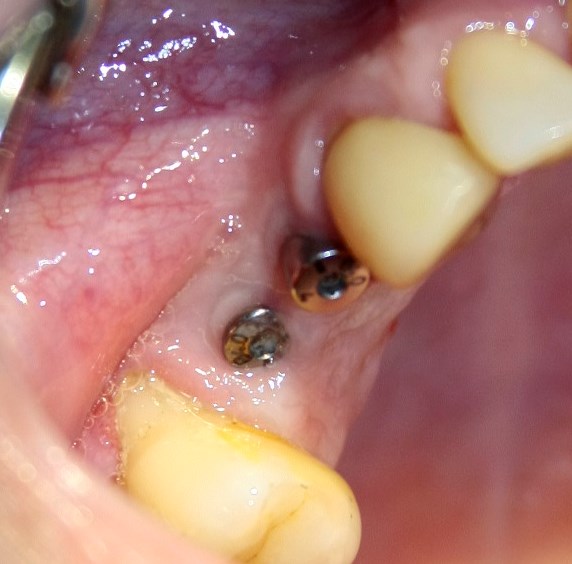

Поэтому после удаления зуба мы ждём, в общей сложности, около 4-8 недель, затем приступаем к имплантологическому лечению. Хотя, иногда бывают ситуации, когда мы делаем синуслифтинг одномоментно с удалением зуба, а сам имплантат ставим попозже:

через 4 месяца: